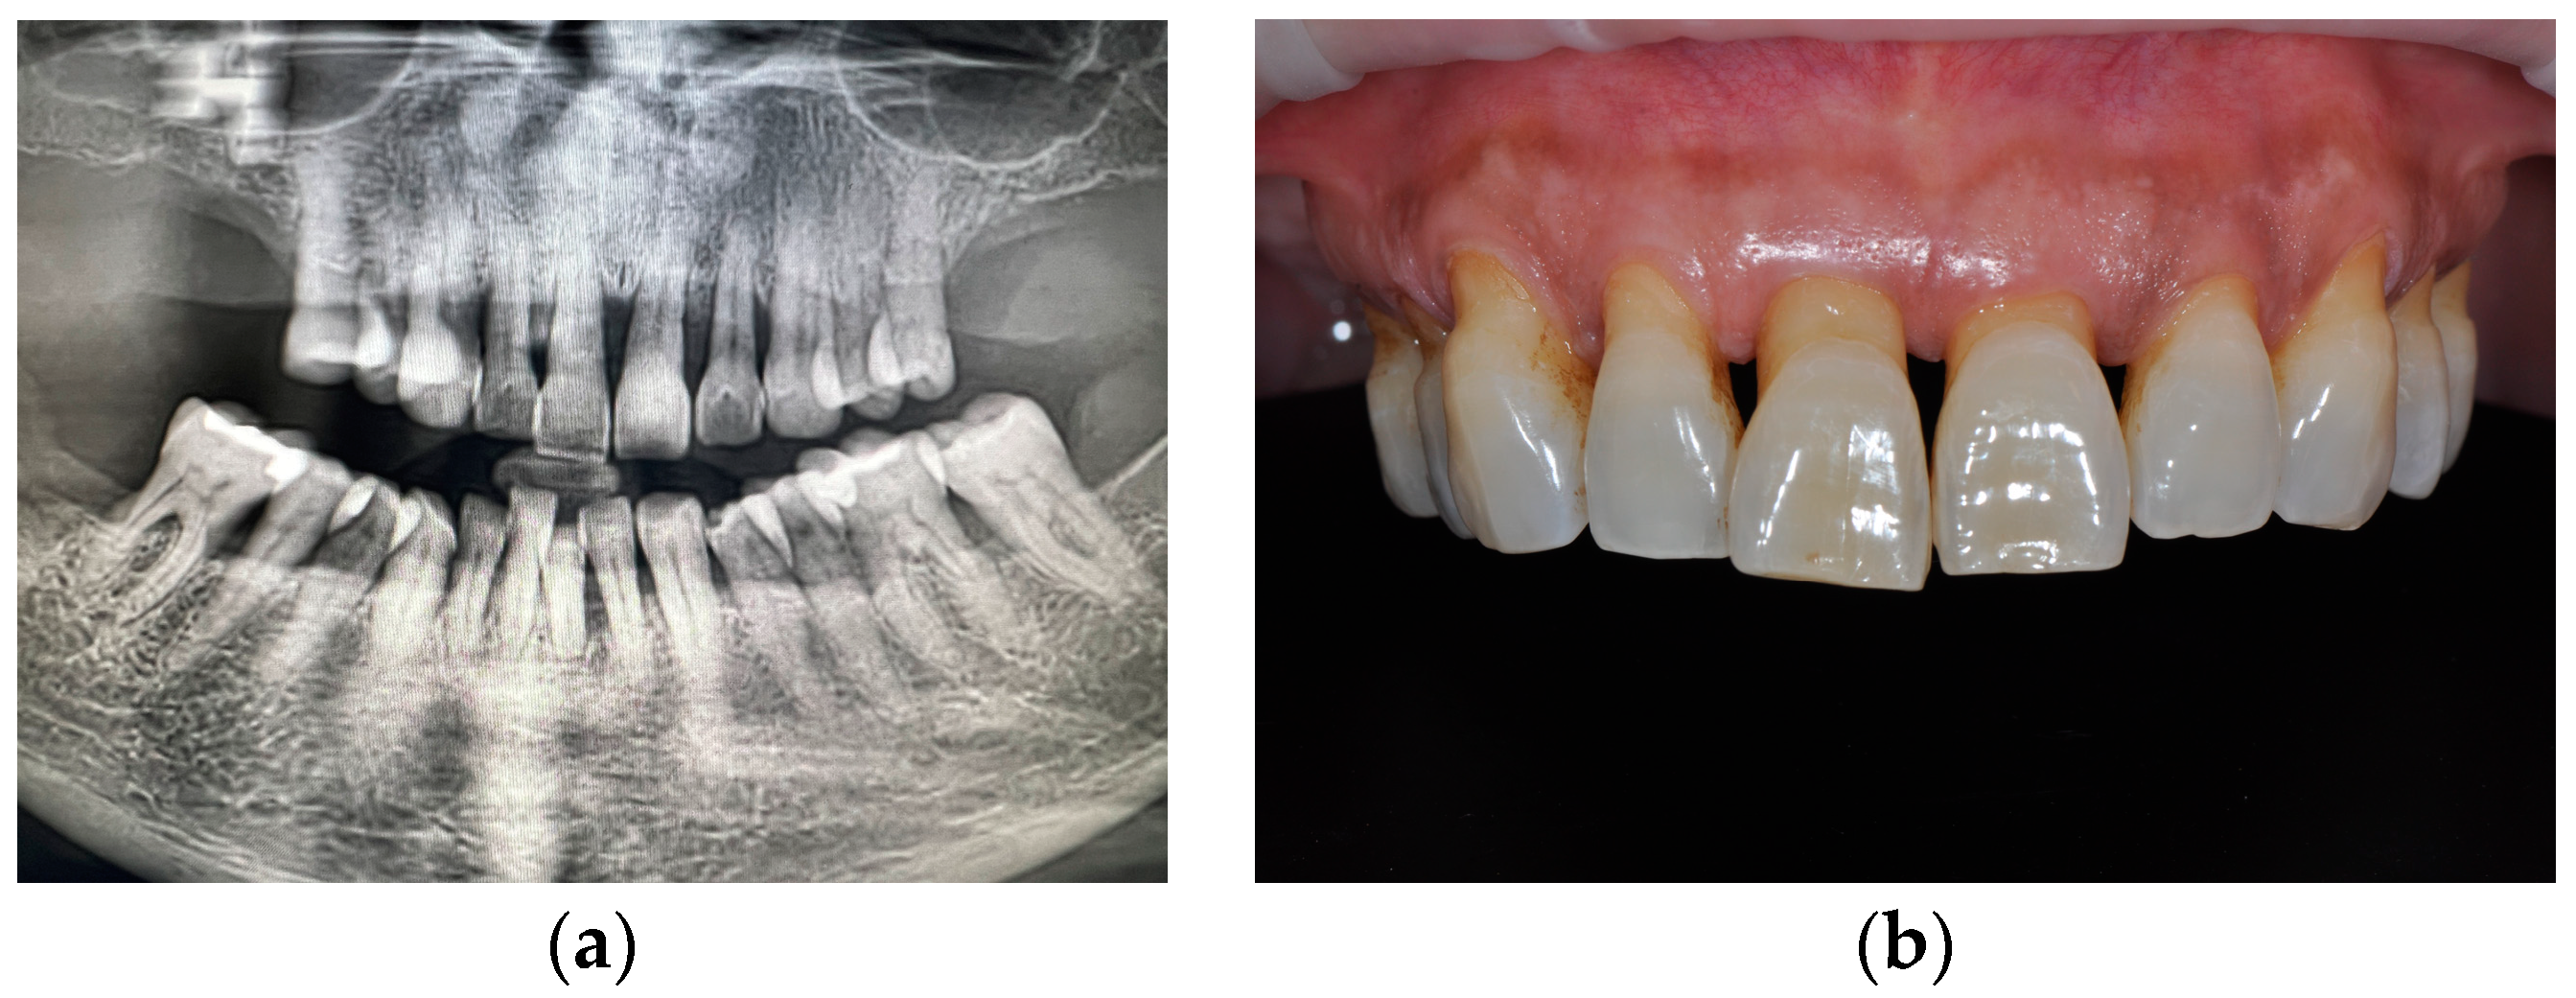

1. Introduction

2. Materials and Methods

2.1. Surgical Phase